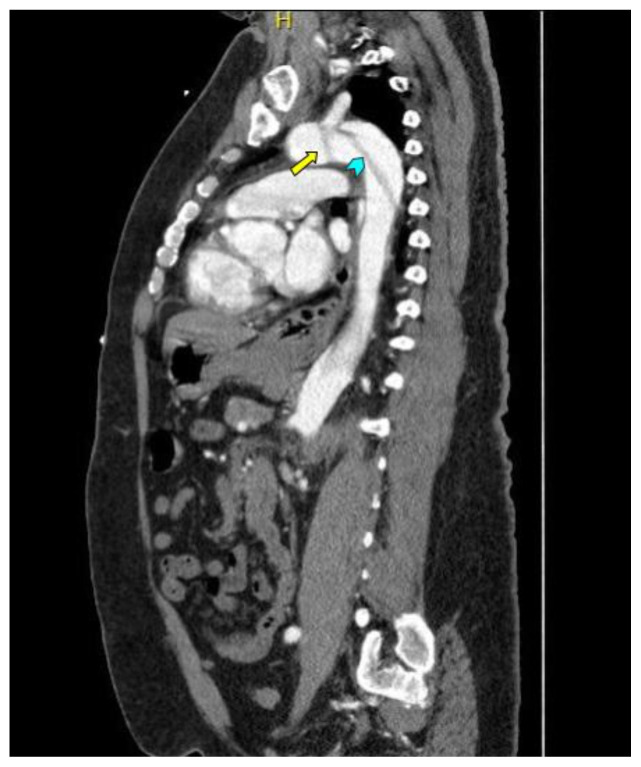

Computed tomography angiography (CTA) of the thoracic and abdominal aorta revealed an aortic dissection of the ascending aorta, with a dissection flap starting from the aortic root/aortic annulus (yellow arrows), extending into the aortic arch (light blue arrowhead) and involving the left common carotid artery (purple arrow), left subclavian artery (pink arrow), extending to the descending aorta (red arrows), and into the bilateral iliacs (green arrows). The true lumen (red star) and false lumen (blue star) created by the dissection flap can best be seen in the axial views. Laboratory findings revealed a mild leukocytosis with a white blood cell (WBC) count of 14.6 (reference range 4.0–10.5 WBC’s × 109 per L), but were overall insignificant with a lactate level of 1.3 mmol/L (0.5–2.0 mmol/L) and a high sensitivity troponin I of 13 ng/L (0–20 ng/L).